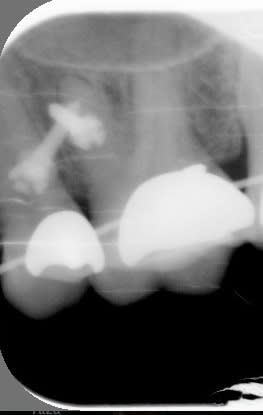

t'es sure que t'as pas une minivis plantée dans la racine mésiale de 26?

> t'es sure que t'as pas une minivis plantée dans la racine mésiale de 26?

tu crois?

(tu râles pas, j'ai pris ma radio de ma dent moi même hein, d'où la mauvaise angulation ;-))